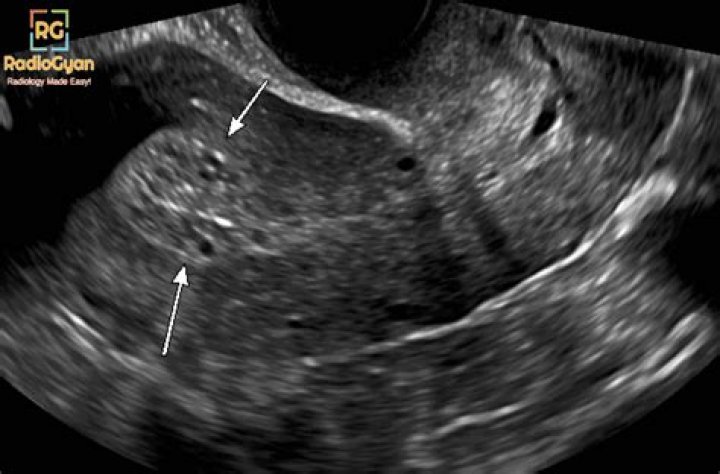

Among postmenopausal women with vaginal bleeding, an endometrial thickness ≤ 5 mm is generally considered normal, while thicknesses > 5 mm are considered abnormal4, 5.

What is the normal size of endometrial thickness?

suggested upper limit of normal is <5 mm. the risk of carcinoma is ~7% if the endometrium is >5 mm and 0.07% if the endometrium is <5 mm. on hormonal replacement therapy: upper limit is 5 mm.

What percentage of endometrial biopsies are cancerous?

Conclusions: In a postmenopausal woman without vaginal bleeding, if the endometrium measures > 11 mm a biopsy should be considered as the risk of cancer is 6.7%, whereas if the endometrium measures < or = 11 mm a biopsy is not needed as the risk of cancer is extremely low.